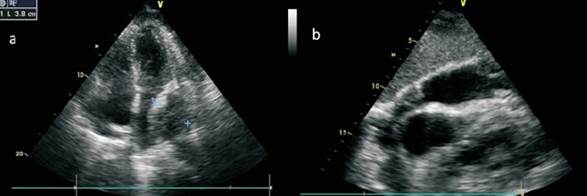

Se decidió realizar un ecocardiograma transtorácico (ETT), el cual confirmó la presencia de un derrame pericárdico severo, a predominio posterior, y una gran masa intrapericárdica de 80 por 38 mm aproximadamente, con múltiples imágenes nodulares a nivel del pericardio parietal. Ventrículo izquierdo de dimensiones normales, con fracción de eyección preservada. Vena cava inferior francamente dilatada, con colapso inspiratorio disminuido, sugestivo de presiones auriculares derechas elevadas. También se observó un derrame pleural izquierdo significativo con atelectasia pasiva a dicho nivel (figura 1).

Figura 1: a) Ecocardiograma transtorácico vista apical cuatro cámaras: se observa gran masa pericárdica comprimiendo la aurícula izquierda. b) Vista subcostal que muestra un derrame pericárdico severo y múltiples masas nodulares localizadas a nivel pericárdico.